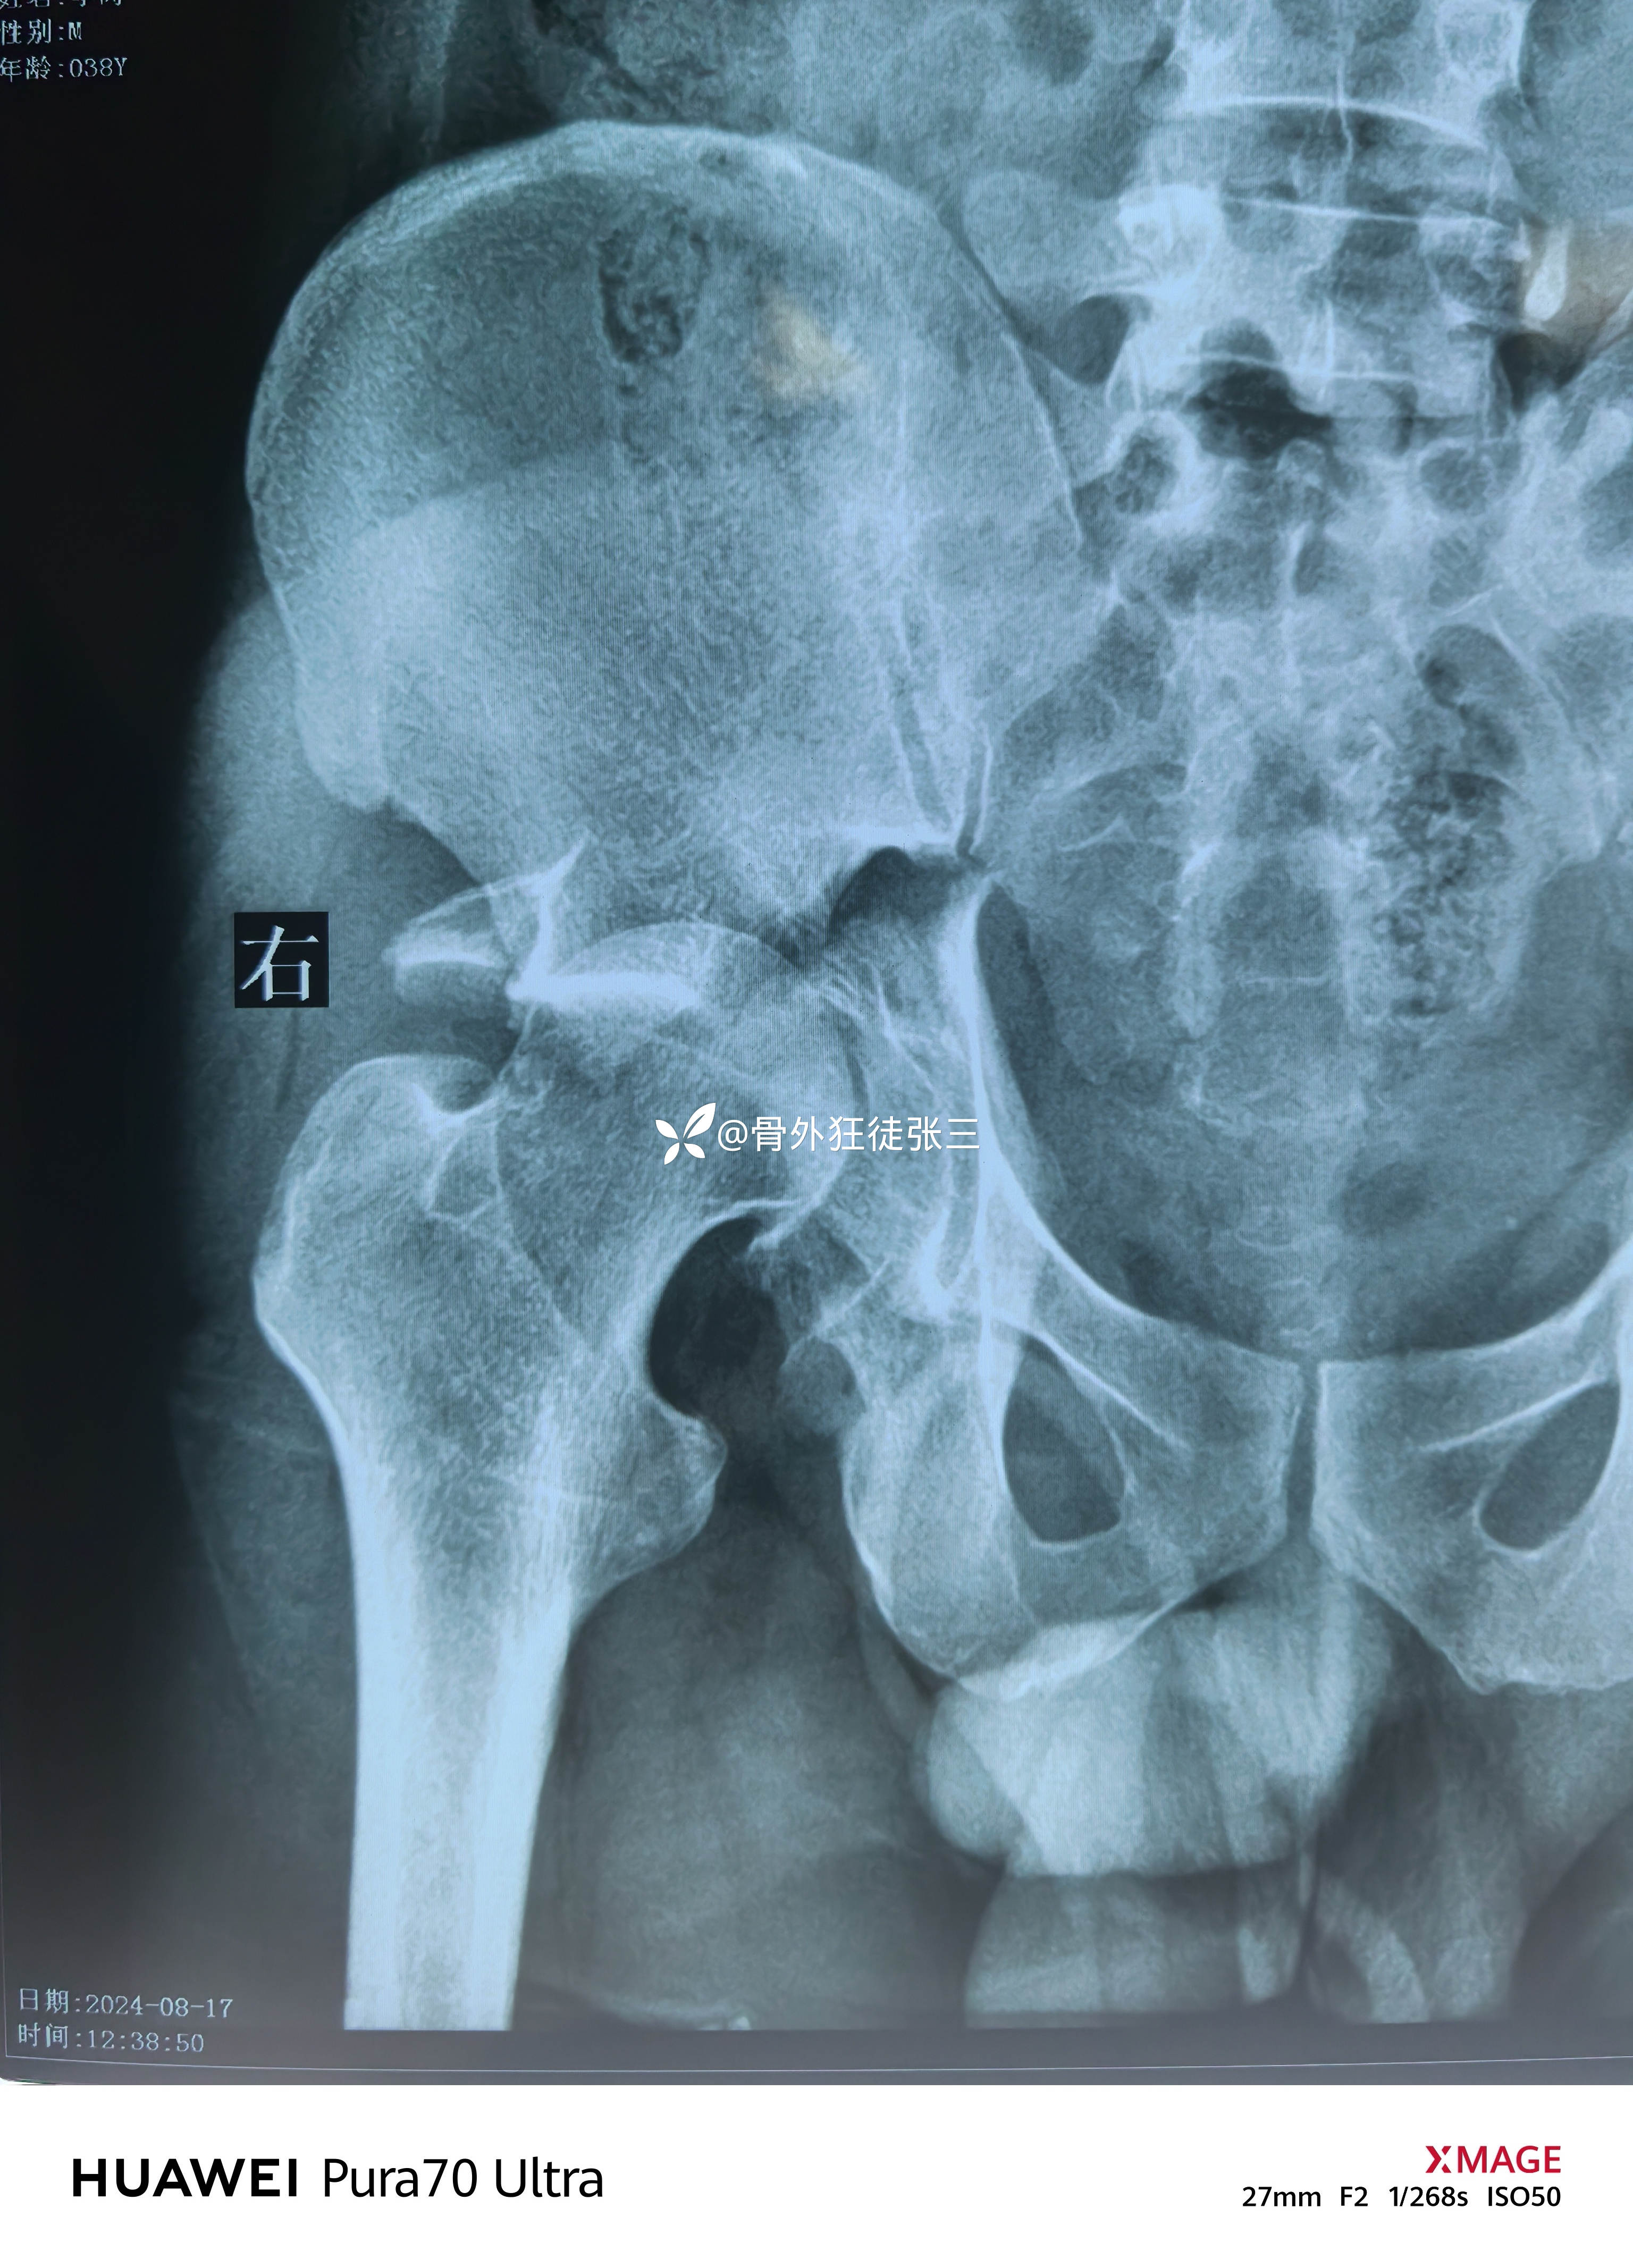

髋关节脱位合并髋臼骨折

髋关节脱位

给予股骨髁上骨牵引

脱位纠正良好

髋臼骨折拟二期手术